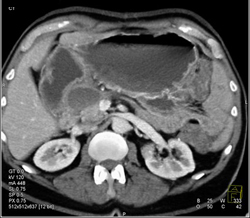

Diagnosis

Pseudocyst